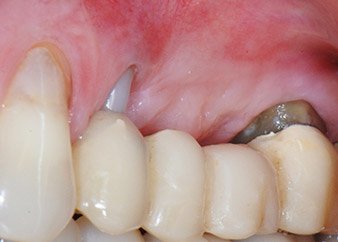

След един месец, в деня на операцията, болката и възпалението в зъб 24 е минимално, но подвижността в Miller class 2 е на лице. След отваряне на ламбата и почистването на периапикалната и перирадикуларната тъкани, обхватът на костния дефект стана очевиден (Фиг. 2 и 3).

В букалния корен, цялата вестибуларна и дистална кост липсва. Захващането е значително ограничено до палатиналния корен, подчертавайки предварително лошата прогноза. Зъб 27 също откри намалено хоризонтално захващане и минимално апикално разреждане (Фиг. 1) без клинични симптоми.

Фигури 17 и 18 показват клиничния резултат два месеца след операцията. Зъб 24 показва намалена подвижност на Милър клас 1 и меките тъкани не са възпалени. Сондирането е избегнато на този етап, за да се избегне повторно възпаление и нарушение на епителната надстройка. Планиран е контролен преглед за повторно отваряне и поставяне на оздравителни абатмънти, шест месеца след поставяне на имплантите.